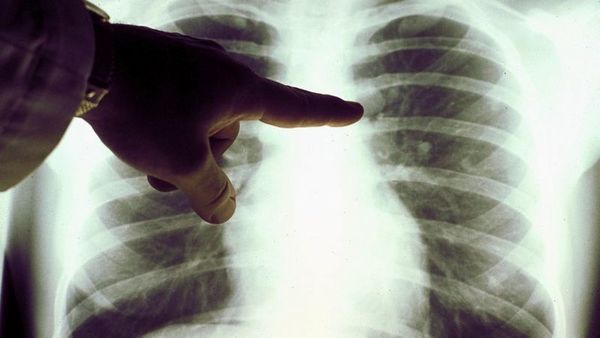

LONDRES. La cadena de noticias BBC Mundo publicó un extraño caso de la curación de un linfoma de Hodgkin por la covid-19. El medio refiere que se acaba de ...[Leer más]